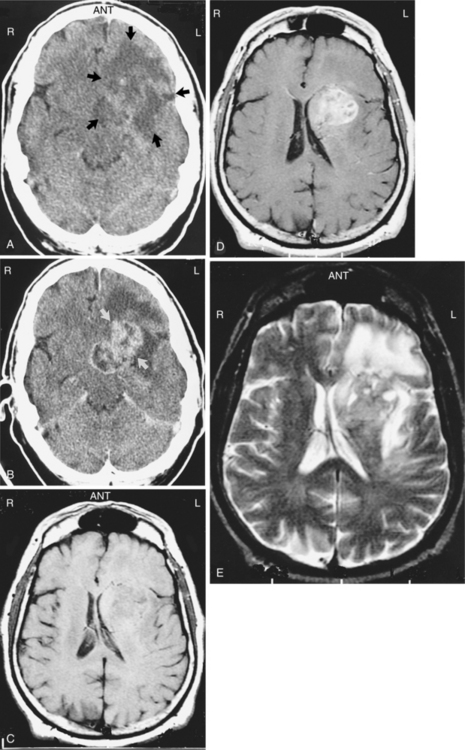

Pathogenesis.: Low-grade astrocytomas include grades I and II. Grade I includes pilocytic astrocytoma (composed of fiber-shaped cells), sometimes termed juvenile astrocytoma, and is considered benign by some and malignant by others.73,133 Grade I astrocytoma grows slowly and often becomes cystic. It is composed of astrocytes with densely staining nuclei and scanty cytoplasm and is usually relatively acellular. The cells are uniform and closely resemble mature resting or reactive nonanaplastic astrocytes (well differentiated). Mitoses are absent or very rare.59,73 Although these are slow-growing tumors, they may become large.4 See Fig. 30-4 for a photograph of a well-differentiated astrocytoma. Grade II astrocytomas may be diffuse, infiltrative, and/or fibrillary, and have more anaplastic features. Fibrillary refers to the neuroglial fibrils. Other types are protoplasmic (cells that consist largely of protoplasm) and gemistocytic (large, densely packed cells with a globoid appearance).133 There is moderate cell density. Fig. 30-5 shows the appearance of computed tomographic (CT) and MRI astrocytoma scans with and without the use of contrast. The contrast agent, such as gadolinium, distinguishes the edema from the actual tumor. The larger the extent of the edema after administration of an intravenous contrast agent, the more malignant the lesion is likely to be.83 Cerebral astrocytoma presents as a solid, grey mass with indistinct boundaries. Differentiation falls somewhere within a spectrum from well-differentiated (grade I) tumors to more anaplastic (grade II) tumors.45 Astrocytomas in the cerebellum are often cystic and well circumscribed.

Figure 30-5 Astrocytoma. These contrasted and noncontrasted computed tomographic (CT) and magnetic resonance imaging (MRI) scans were obtained in the same patient and demonstrate a left astrocytoma with a large amount of surrounding edema. A, The noncontrasted CT scan shows only a large area of low density that represents the tumor and edema (arrows). B, A contrasted CT scan shows enhancement of the tumor (arrows) surrounded by the dark or low-density area of edema. C, A noncontrasted T1-weighted MRI scan clearly shows a mass effect due to impression of the tumor on the left lateral ventricle and some midline shift. D, A gadolinium-enhanced T1-weighted MRI scan clearly outlines the tumor, but the edema is difficult to see. E, A T2-weighted MRI scan shows the tumor rather poorly, but the surrounding edema is easily seen as an area of increased signal (white). (From Mettler FA Jr: Essentials of radiology, ed 2, Philadelphia, 2005, Saunders.)